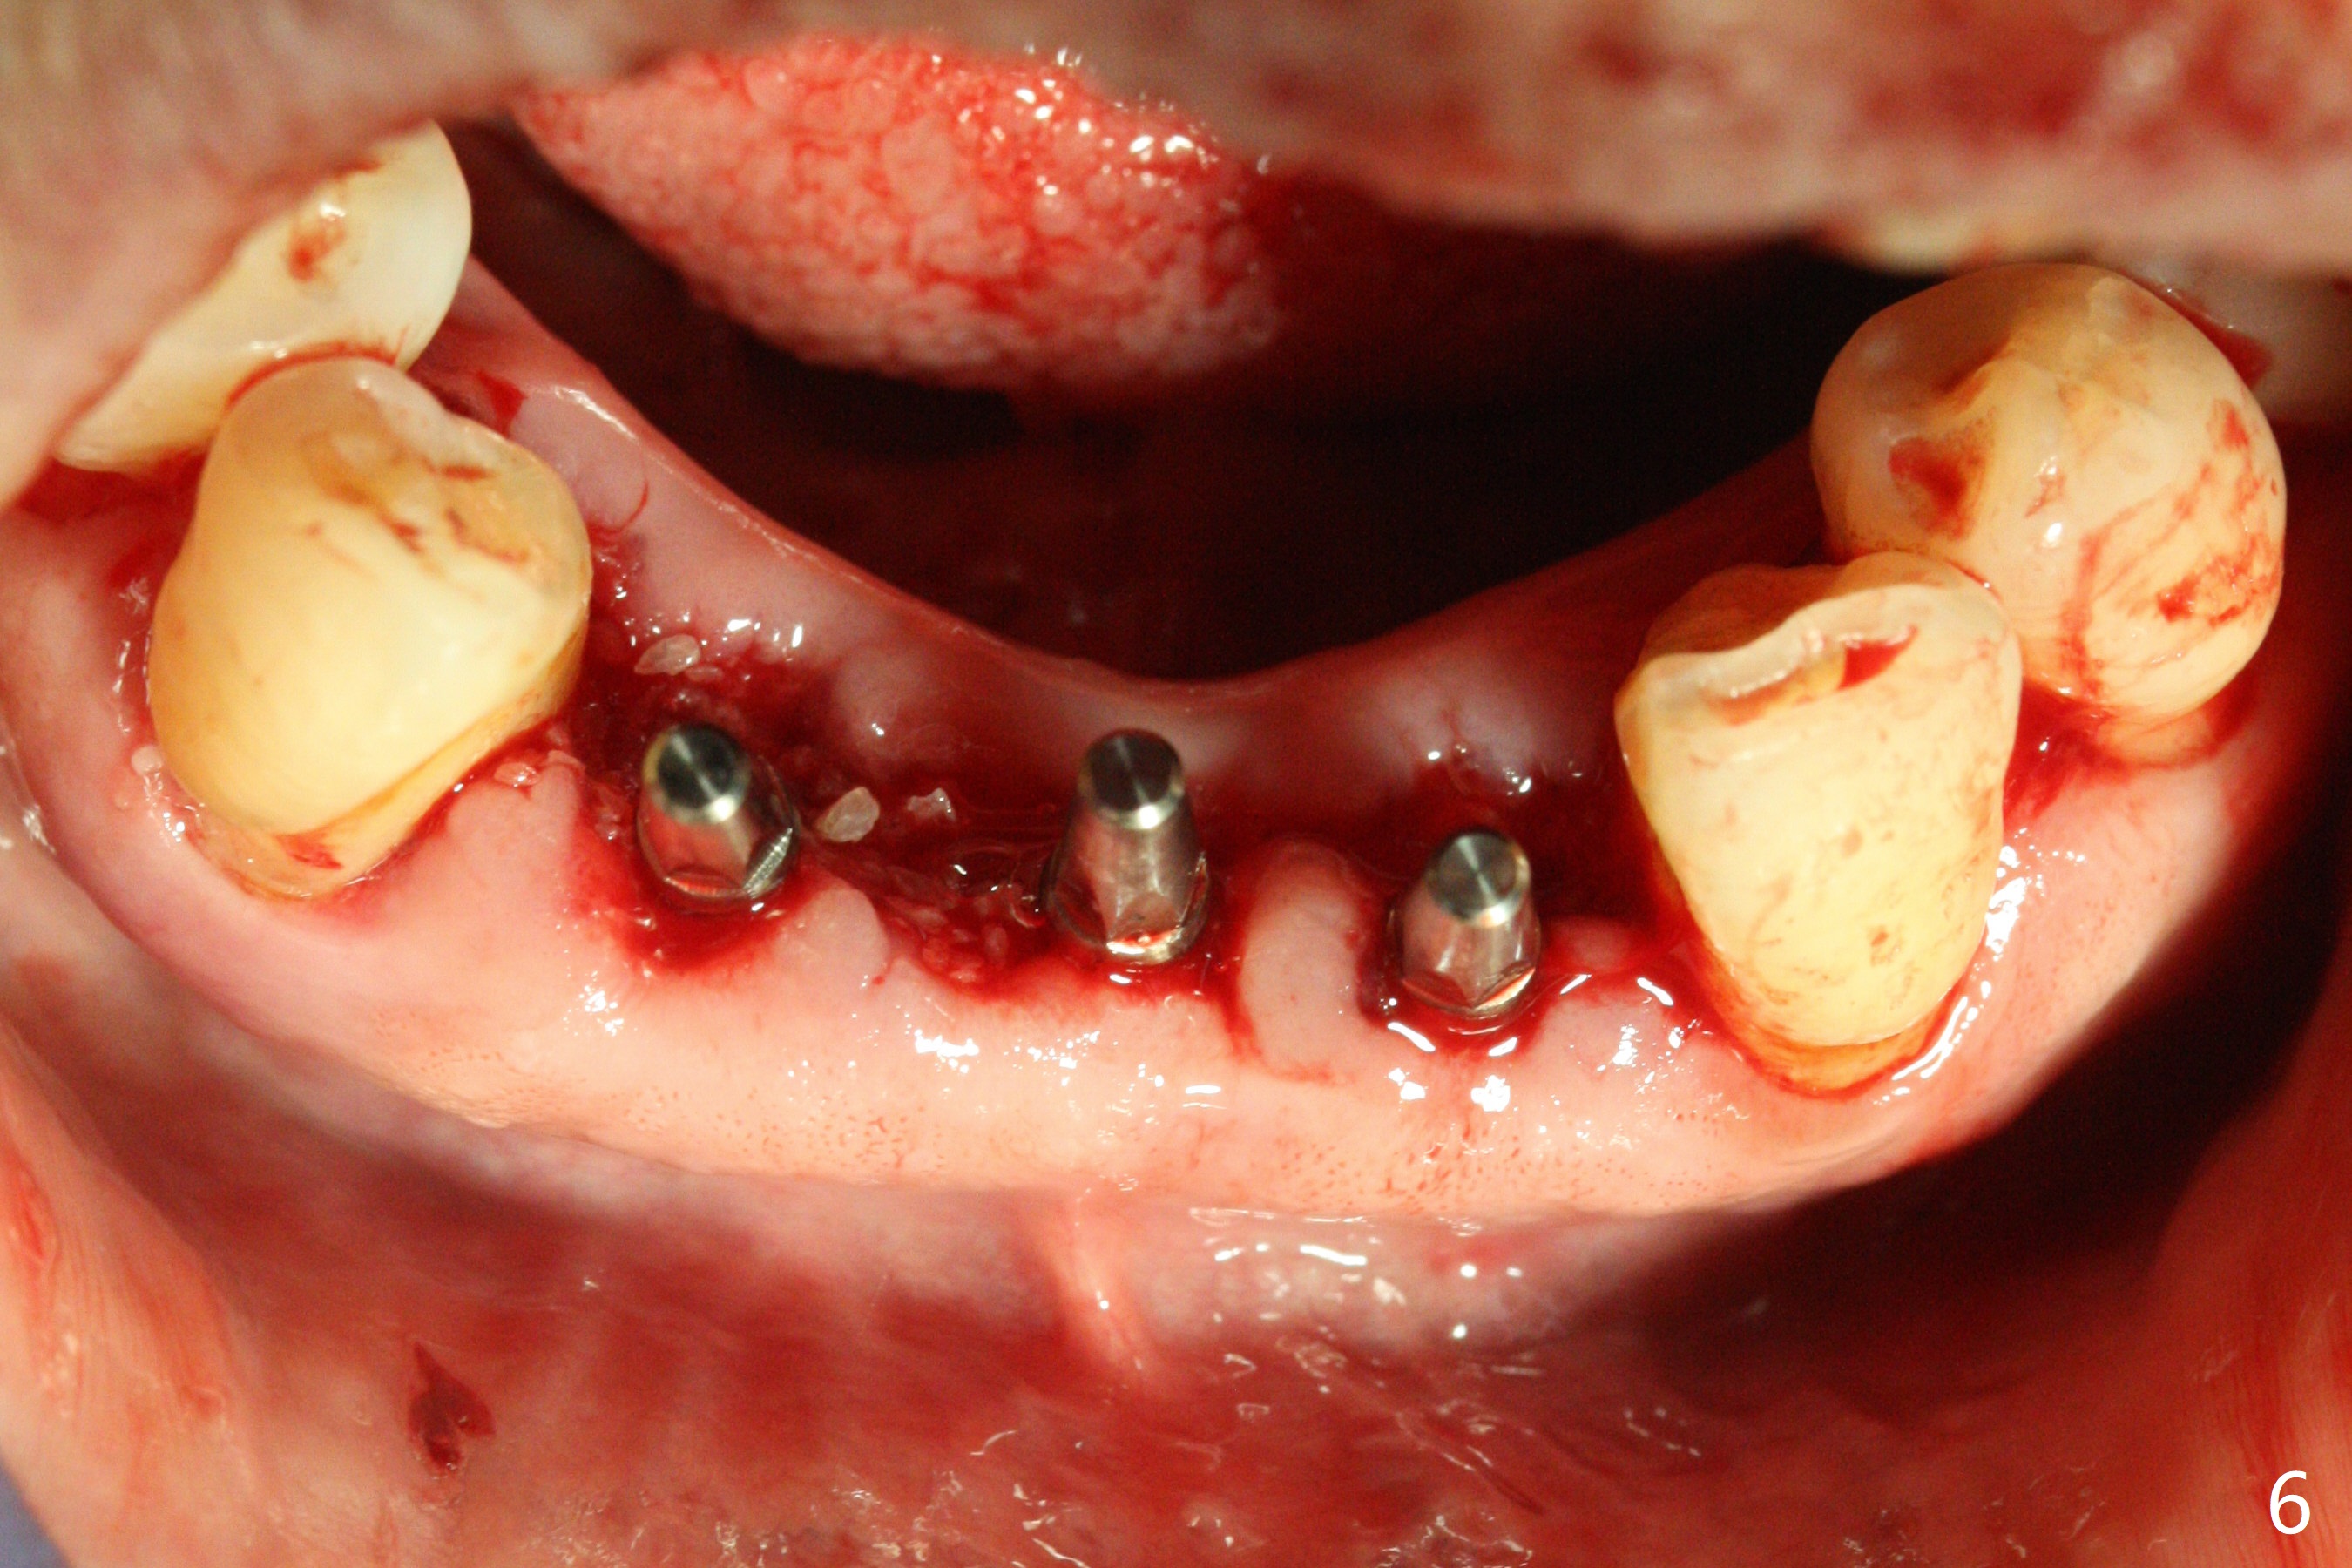

When the patient returns, the tooth #24 has exfoliated, while the ones at #25 and 26 has mobility III (Fig.1). The patient requests the tooth #23 extraction (Fig.2), but not #27. After SRP and extraction, osteotomy is initiated mesial to the sockets #23,25 and 26 (Fig.3,4) with intention to place 3 1-piece implants for 3 incisor crowns (Fig.5,6). Following Vanilla graft (Fig.5 *) a splinted provisional is fabricated to close the sockets (Fig.6). Peri-implant spaces close 5.5 months postop (Fig.7). Impression is taken after reprep for margin and parallelism (Fig.8). The final restoration consists of #23 single unit crown and #24-26 3-unit FPD (Fig.9). It appears that 2.5 mm 1-piece implants are not too small for the lower incisors (Fig.10-12), especially the central one (Fig.11). There may be perforation in the apical half of the lingual plate (L in Fig.10). The patient is not pleased with the shade of the #24-26 3-unit FPD (Fig.13 (6 months post cementation)). There is metal show through the abutments (*).